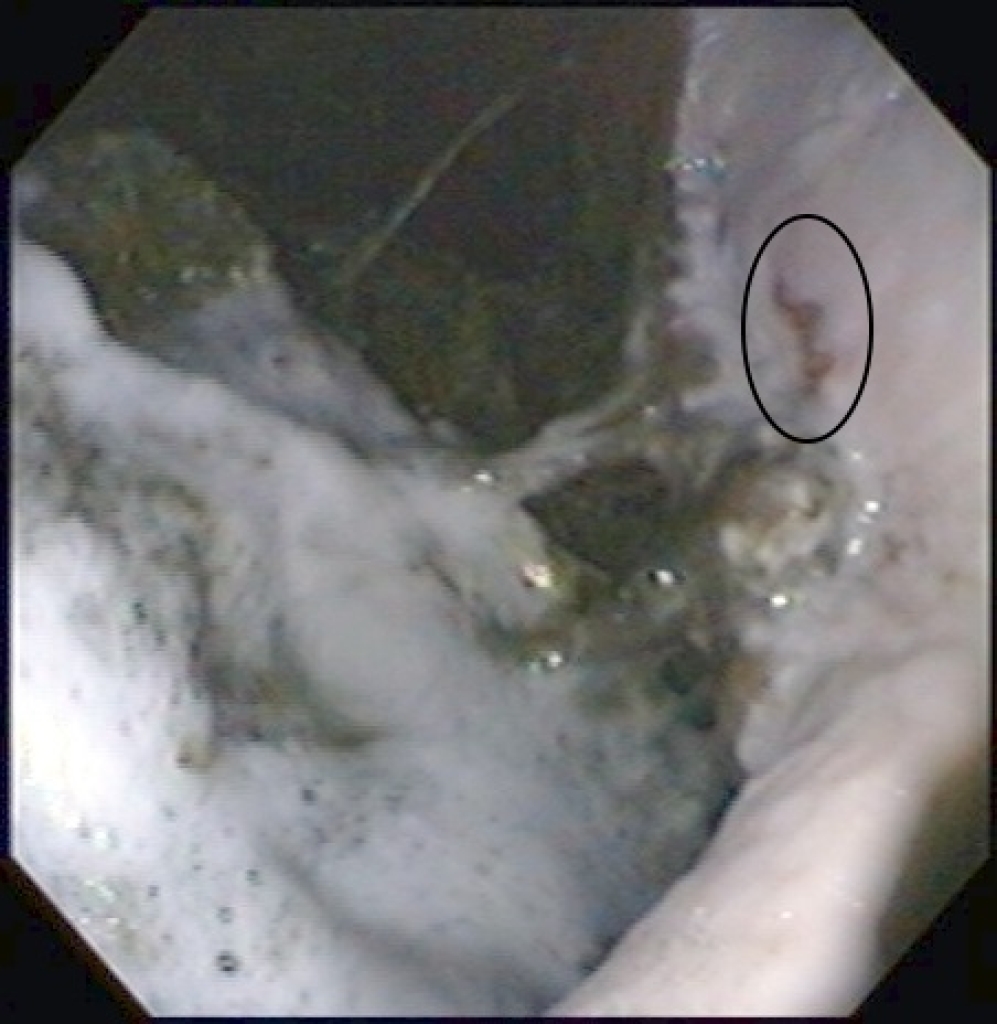

Maagzweer in het verhoornde deel van de maag, net boven de margo plicatus

Foto: Maagzweer in het verhoornde deel van de maag, net boven de margo plicatus

Maagzweren in het verhoornde deel van de maag en op de margo plicatus

Maagzweren in het verhoornde deel van de maag

Maagulcera net boven de margo plicatus